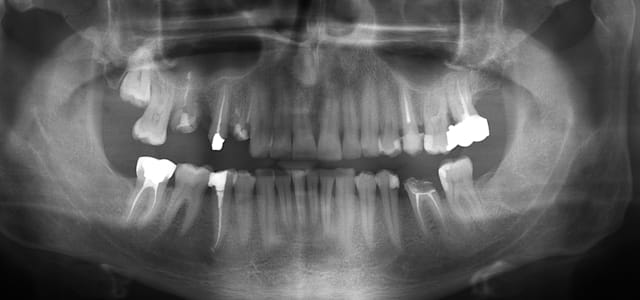

Dans le cadre d'un bilan pré greffe cardiaque, -normalement- il faut avulser toute dent présentant un traitement endo manifestement incomplet.

Je prévois d'avulser 18 16 14 27

Les composites débordants seront repris et la carie sur 35.

47 et 36 sont asymptomatiques et dévitalisées il y a plus de 6 mois, mais le traitement n'est pas top.

De plus l'apex de la 45 semble présenter un halo diffus radioclair.